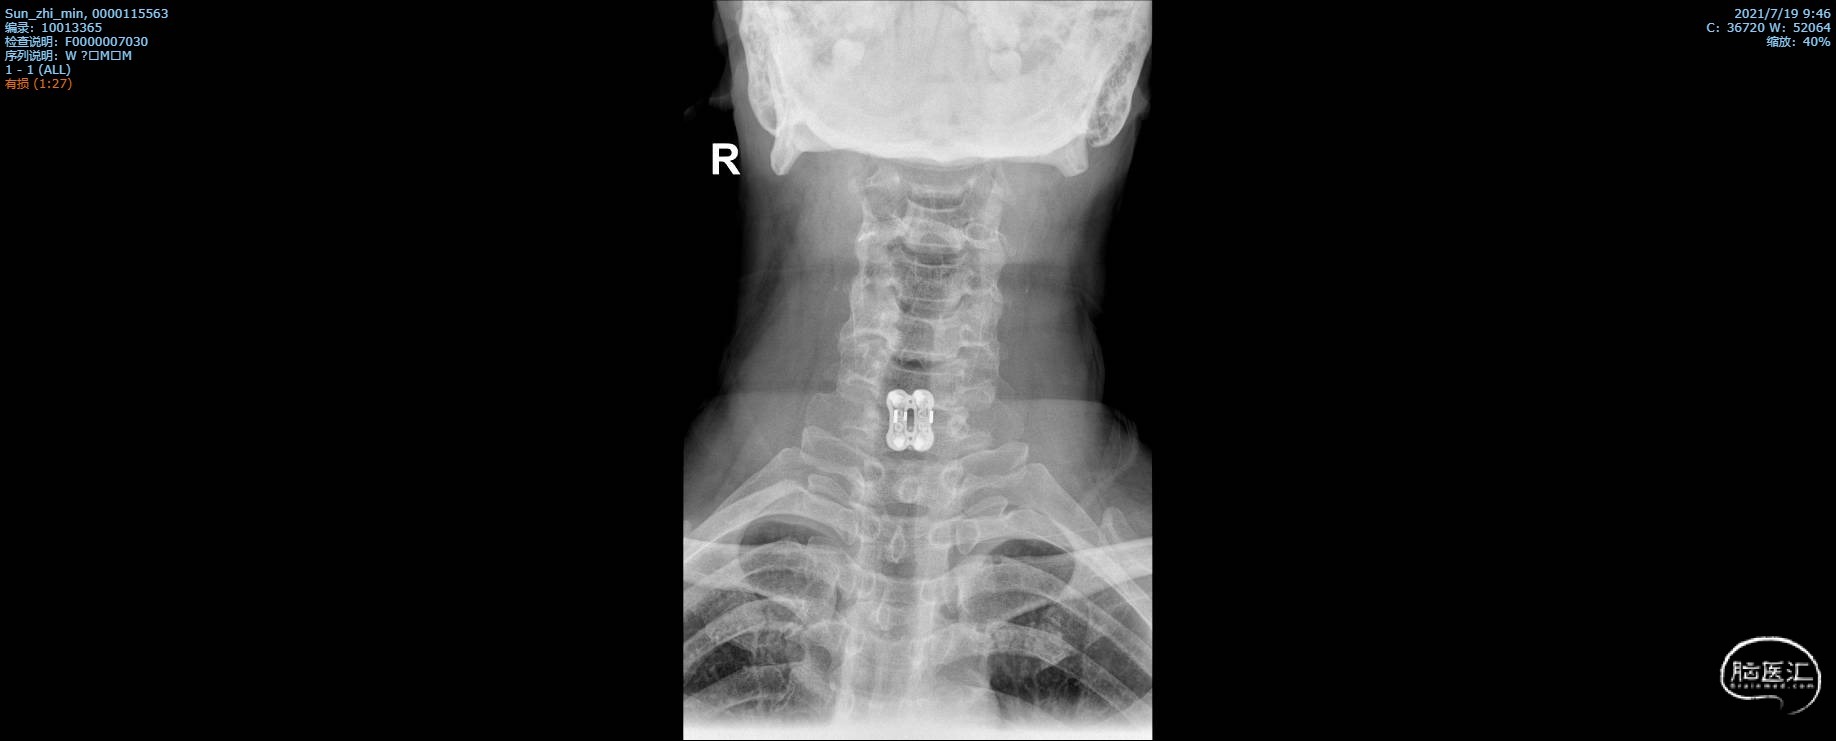

术后颈椎X线片复查

X线正位

X线侧位